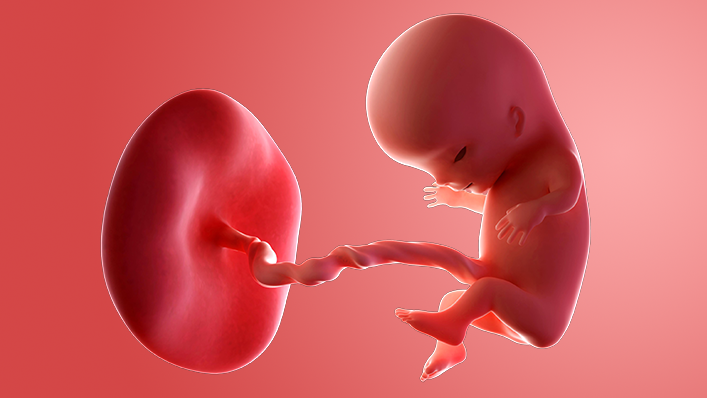

What does my baby look like?

Your baby, or foetus, is now around 22mm long from head to bottom, which is about the size of a strawberry.

The face is looking more recognisable, with eyes protected by eyelids, a little mouth and even a tongue with tiny taste buds.

The hands and feet are developing, but there are no fingers or toes yet, just grooves where they will be.

All the major internal organs – the heart, brain, lung, kidneys and gut – are developing. Bones are starting to form.

Your baby's genitals are also starting to take shape – but you probably won't find out if it's a boy or a girl until your anomaly scan at around 18 to 21 weeks.